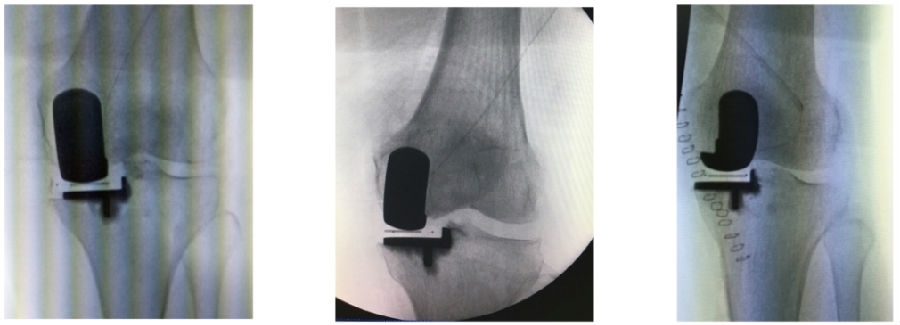

10、核查切骨与规划之间的吻合度

取下导板,取出骨块进行比对。注意对比厚度时要加上软骨的厚度如果吻合度有明显偏差,可以考虑徒手加截。

12、术后拍片

目前,笔者团队已经做了70多例,在早期探索过程中可能会出现一些问题,但是之后基本上都是比较好的,术后片子比较赏心悦目。